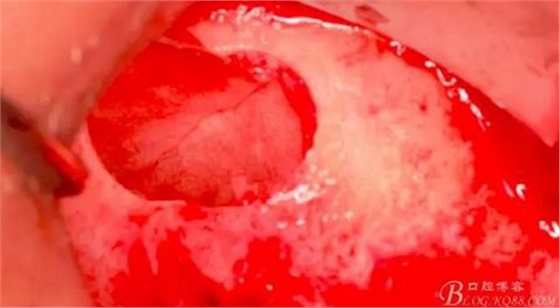

使用窗口擴大鉆,這也是這套工具盒里一個亮點,其前端是圓形高度光滑的,鉆體是有側(cè)切功能的。工作時用光滑的圓頭頂開已經(jīng)剝離的竇膜,用鉆體部分將窗口周邊不規(guī)則的部分磨掉,同時可以擴大窗口。

習(xí)慣性的在竇膜下貼服一張膜保護。